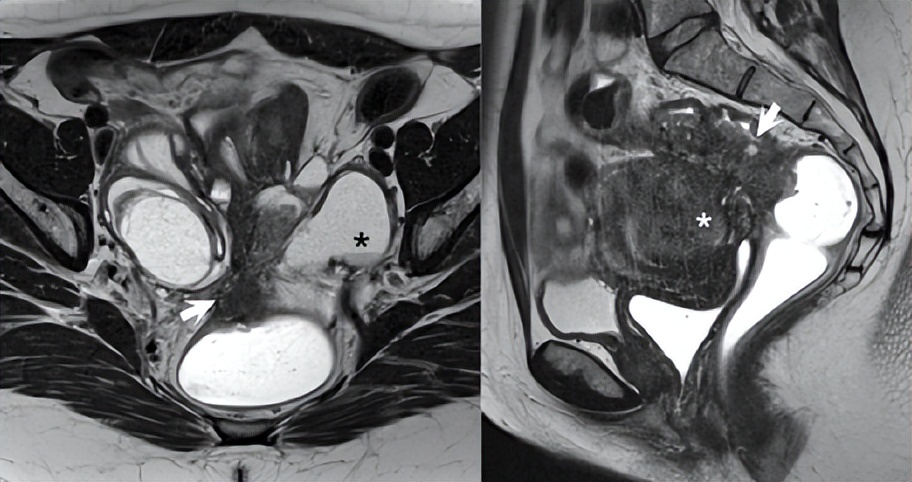

图76.5显示了一例患有严重子宫内膜异位症(AFS IV)的41岁女性患者的(A)轴位和(B)矢状位T2WI。在(A)中,左侧子宫内膜瘤中可见T2阴影(黑色*),上直肠阴道隔/囊膜中有T2低信号深度浸润性子宫内膜异位症(箭头)。在(B)中,可见狭窄的直肠乙状结肠状肠内深度浸润性子宫内膜异位症(箭头所示),伴有子宫腺肌症后壁增厚(白色*)。

▲ 图76.5